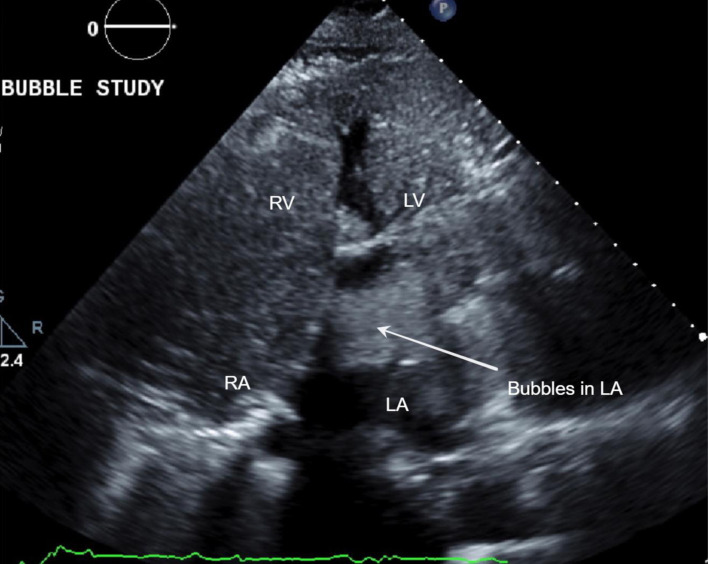

呼吸困难是一种令人痛苦的症状,表现为直立时呼吸困难,躺下时症状明显改善。与仰卧位时呼吸困难加重的正位性呼吸困难形成鲜明对比的是,POS 在从躺下到站立的过程中会出现血氧饱和度降低的独特症状。这种综合征症状微妙,给诊断带来了挑战,需要临床高度怀疑才能准确识别。在此,我们介绍了一例病史复杂的 79 岁女性患者,其主要病史包括深静脉血栓(DVT)和随后的肺栓塞(PE),需要长期服用华法林进行抗凝治疗;乳腺癌肿块切除术和化疗后病史;高血压和慢性肾脏疾病(CKD)。患者因持续低氧血症和提示 POS 的临床特征从一家生活机构入院。尽管进行了全面的体格检查和常规实验室检查,但未发现明显异常。然而,超声心动图检查发现了严重的卵圆孔未闭(PFO)和右向左分流,证实了 POS 的诊断。随后,医生使用 GORE CARDIOFORM 室间隔封堵器对 PFO 进行了经皮封堵,透视检查证实封堵器成功置入了房间隔内。值得注意的是,患者术后的氧合情况明显改善,并在两天内出院。POS 虽然罕见,但由于其可能导致相当高的发病率和死亡率,因此具有重要的临床意义。POS 的病理生理学基础在于肺血流和全身血流之间的不协调,最终导致患者在采取直立姿势时出现动脉饱和度降低。及时识别和干预对于减轻症状负担和避免相关并发症的恶化至关重要。早期诊断有助于实施有针对性的治疗策略,从而缓解呼吸困难,防止该综合征引发不良后遗症。因此,提高医护人员对 POS 细微表现的认识对于加快适当的管理和优化患者预后至关重要。

Platypnea-orthodeoxia syndrome (POS) is an uncommon yet clinically significant medical phenomenon characterized by dyspnea, a distressing symptom manifesting as breathlessness upon assuming an upright position, which notably improves upon reclining. In stark contrast to orthopnea, where dyspnea worsens in a supine position, POS uniquely presents with decreased blood oxygen saturation upon transitioning from lying down to standing up. This syndrome poses diagnostic challenges due to its subtle symptomatology and requires a high index of clinical suspicion for accurate identification. Herein, we present a case of a 79-year-old female with a complex medical history, notably encompassing deep vein thrombosis (DVT) and subsequent pulmonary embolism (PE) necessitating long-term anticoagulation with warfarin, a history of breast cancer status post lumpectomy and chemotherapy, hypertension, and chronic kidney disease (CKD). The patient was admitted from a living facility with persistent hypoxemia and clinical features suggestive of POS. Despite comprehensive physical examination and routine laboratory investigations, no overt abnormalities were discerned. However, echocardiography unveiled a severe patent foramen ovale (PFO) with right-to-left shunting, corroborating the diagnosis of POS. Subsequently, percutaneous closure of the PFO using the GORE CARDIOFORM septal occluder was performed, with fluoroscopy confirming successful device placement within the atrial septum. Remarkably, the patient demonstrated significant improvement in oxygenation post-procedure, prompting her discharge within 2 days. POS, though rare, holds substantial clinical significance owing to its potential to precipitate considerable morbidity and mortality. The pathophysiological basis of POS lies in the discordance between pulmonary and systemic blood flow, culminating in arterial desaturation upon assuming an upright posture. Timely recognition and intervention are imperative to mitigate symptom burden and avert the progression of associated complications. Early diagnosis facilitates the implementation of targeted therapeutic strategies, thereby alleviating dyspnea and forestalling adverse sequelae stemming from this syndrome. As such, heightened awareness among healthcare practitioners regarding the nuanced presentation of POS is paramount to expedite appropriate management and optimize patient outcomes.